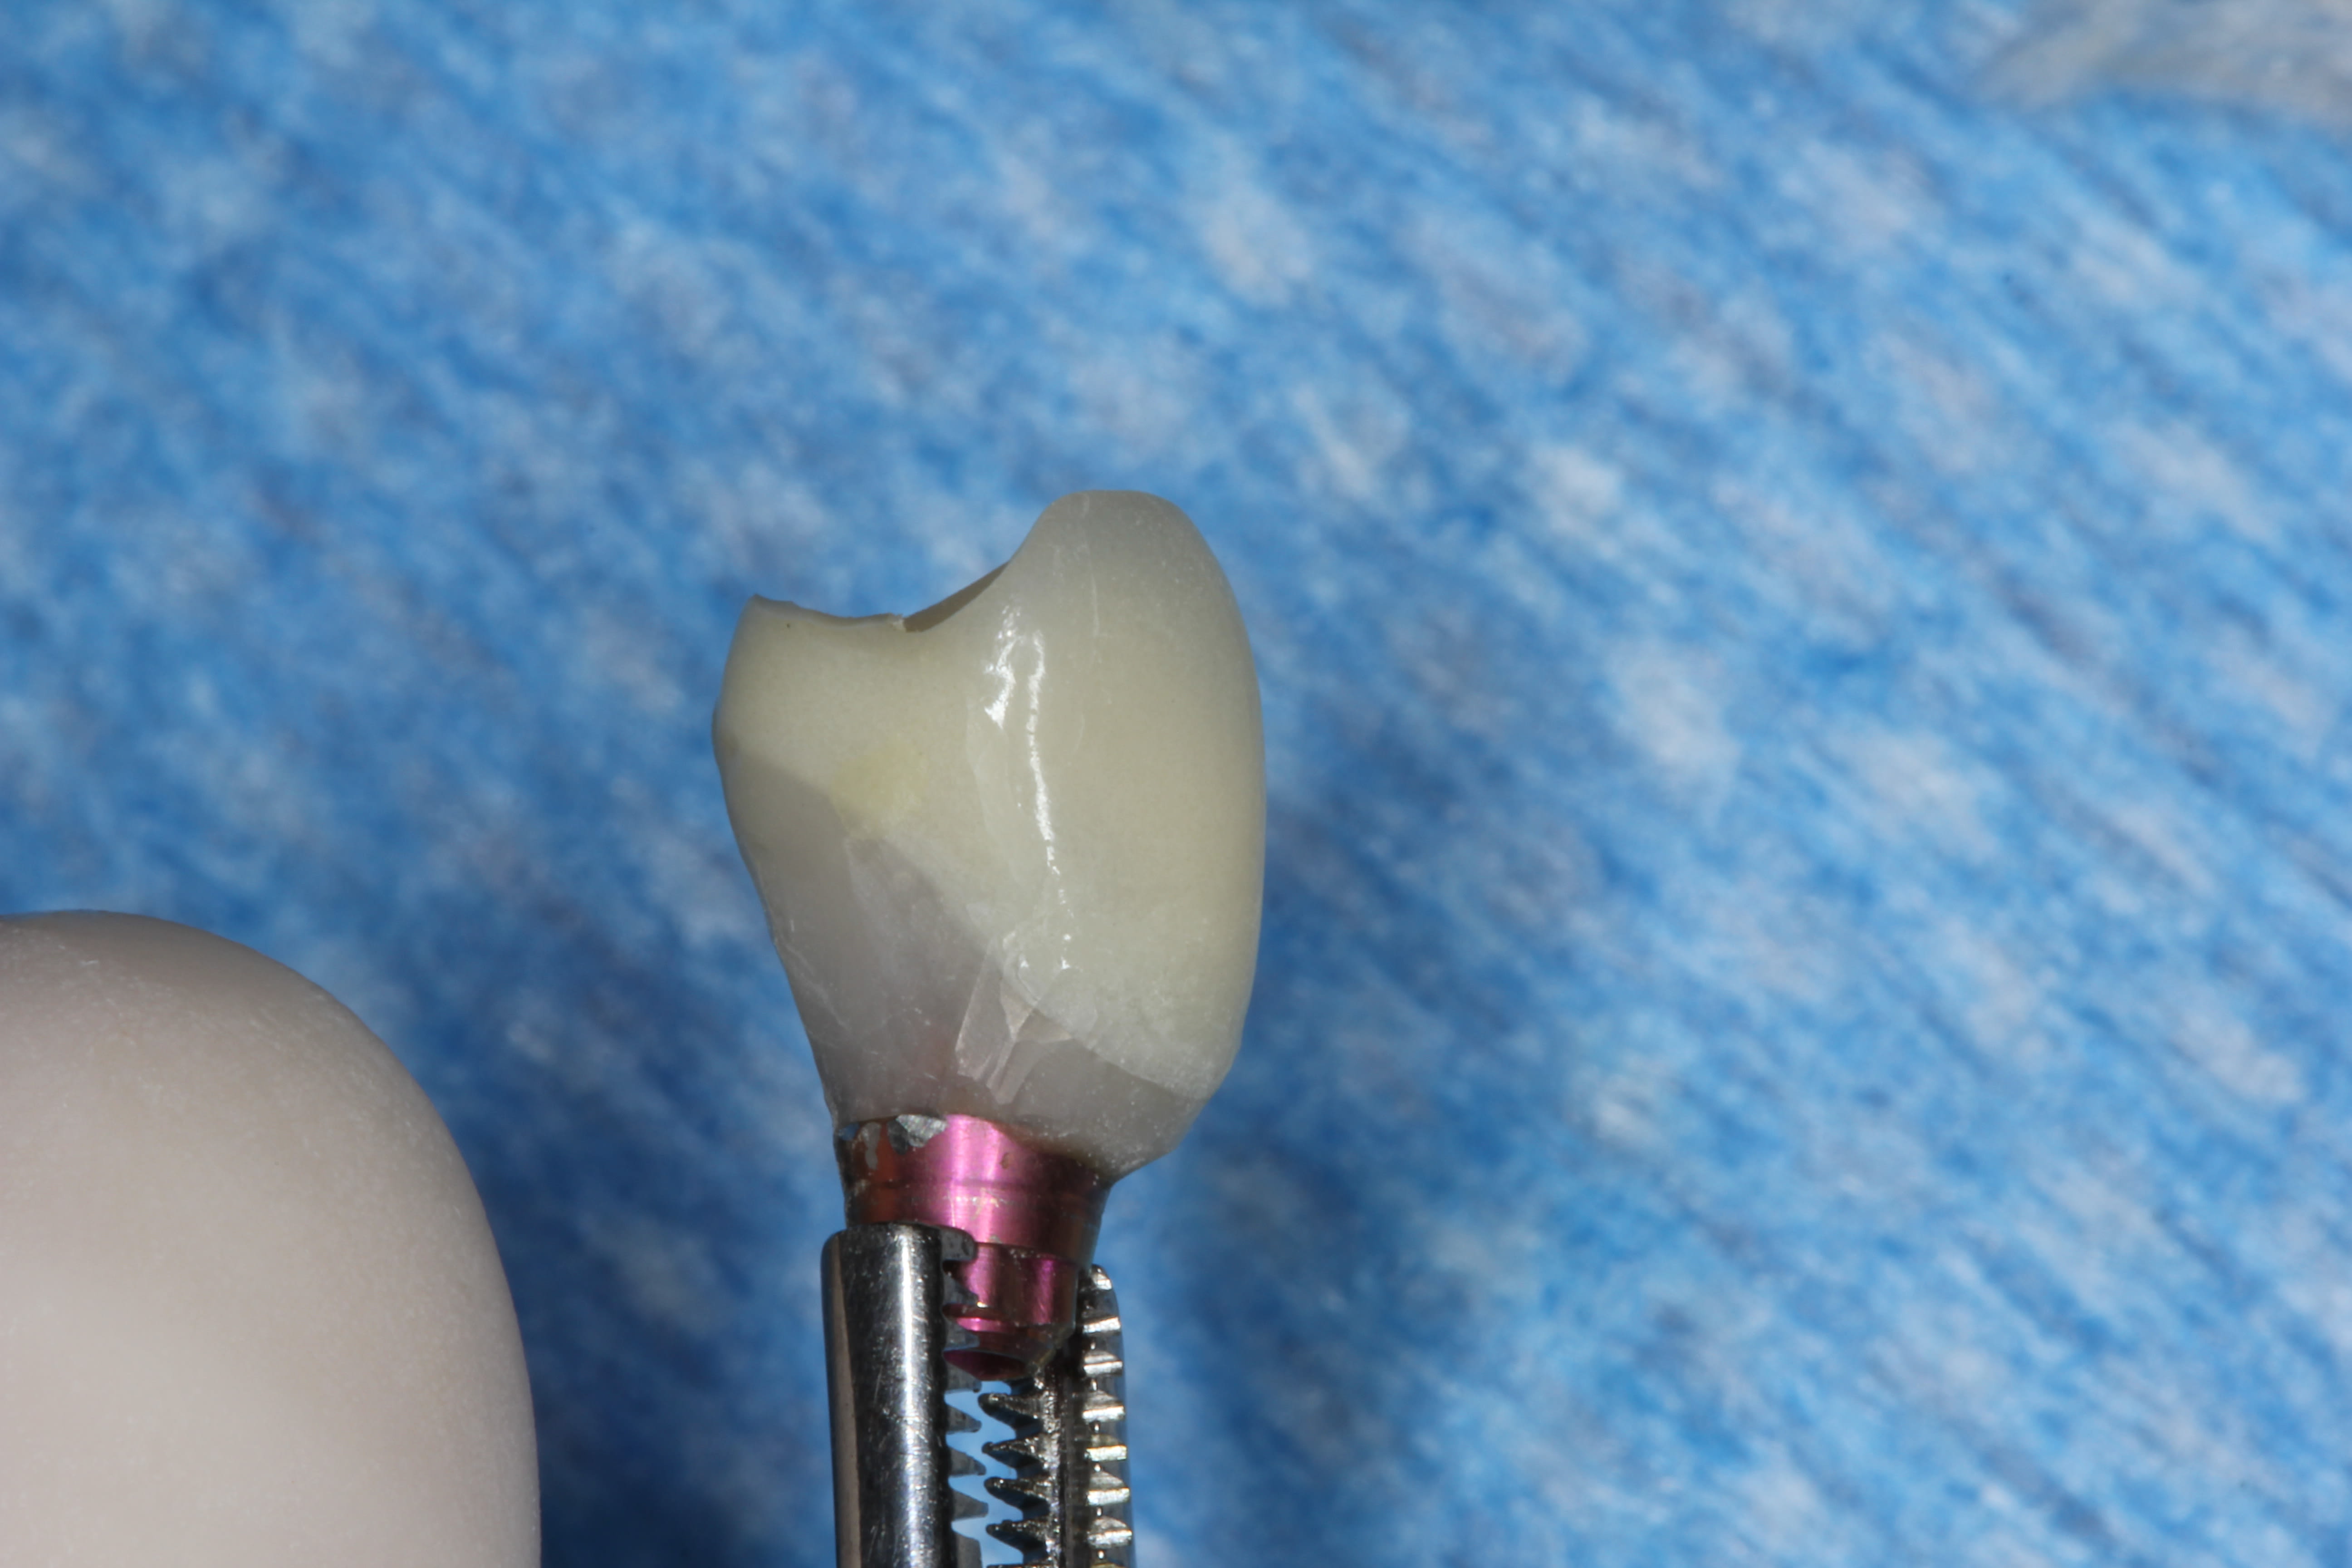

One month later, the custom UCLA abutment (Figure 33) was attached to the fixture using a platform-switched connection, with an insertion torque of 35 Ncm. The final PFM crown was cemented using methylmethacrylate (C&B-Metabond® Quick! Cement System, Parkell, www.parkell.com). The occlusion and the patient’s nightguard were checked and adjusted to the new restoration.

The final open-tray polyvinylsiloxane impression (Aquasil®, DENTSPLY International, Inc, www.dentsply.com) was also obtained at Visit 3. The impression coping was radiographically verified for accurate seating. The fixture analog was placed into the laboratory model, and a stock abutment (Genesis) was used by the laboratory to create a PFM crown with a screw-access hole in its occlusal surface (Figure 46).

In the prosthetic phase, the restorative dentist chose to use an indirect cementation technique to minimize the risk of cement entrapment/sepsis if the crown were to be cemented intraorally. In August 2012 the abutment and crown were tried in and, once proper seating and fit had been verified radiographically (Figure 47), the abutment was removed and the crown cemented extraorally with resin-modified glass-ionomer cement (FujiCem™, GC America, www.gcamerica.com). After removal of excess cement, the abutment–crown unit was then seated intraorally and torqued into the implant fixture to 35 Ncm using the standard platform-switched connection for this stock abutment. The access hole was sealed with Teflon tape and, after etching with 9.5% hydrofluoric acid, filled with nanohybrid composite resin (Renamel® NANO™, Cosmedent, www.cosmedent.com). The crown was then contoured, adjusted, and polished.